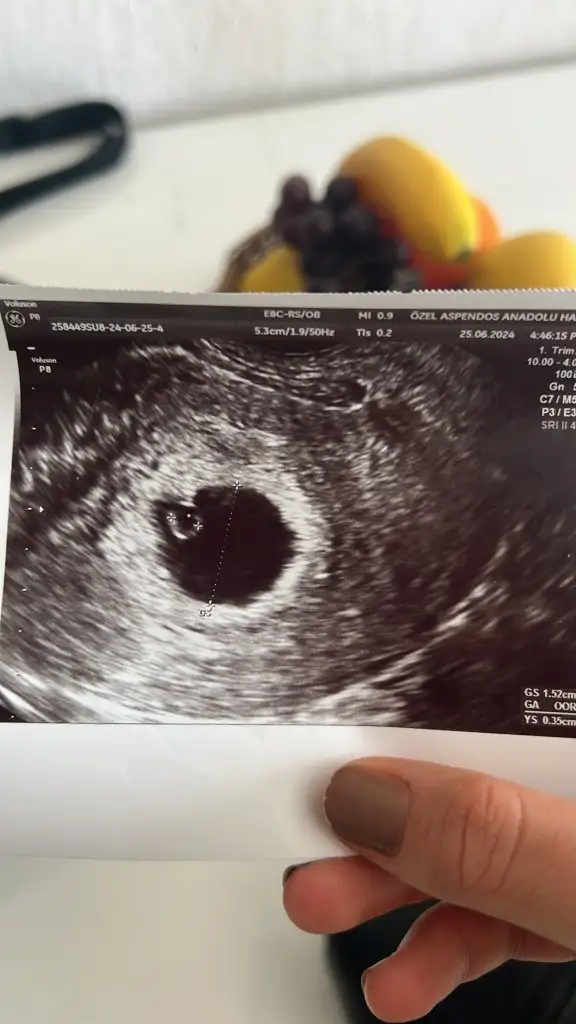

Daha kese 1.5 cm doktorlar 2 cm e kadar yolk sacın bile gözükmeyeceğini düşünüyor. Bence henüz olumsuz düşünülecek birşey yokKızlar son adet 3 Mayıs kesem 20 mm yolk saç var ama bebek yok doktorum başından beri betaya göre değerlendirdiğini için olumsuz konuşuyor betam 46660 çıktı bu haldeyken bebek görünmesi lazımdı dedi ve kese boyutun normal haftasına göre mutlaka bebek görünmeliydi gelişmemiş muhtemelen diyip kürtaj önerdi başına gelen var mı lütfen yardımcı olun ümidim bitti

Yok kese her gittiğim de düzenli gelişiyor hatta yolk sac da sonradan çıktı doktora göre keseye göre gec döllenme imkansız dedi iyice karıştı kafam . Fotoğraftaki ilk gözüken direk kürtaj dediği kese 4 gün sonrada yukarıdaki fotoğraftaki gibi yolk sac görüldübenim son regl 4 mayıs. 5+3te kesem 1.25 cm iken ne bebek ne yolk sac vardı bende. pazartesi günü 7+6 da yani 10 gün sonra bebek ve kalp atışı görüldü. gec döllenme olabilir yani kese boyu hala kücük bence. he kese gelişmiyorsa o zaman bilemem.

kaç cm burada göremiyorum ama kese boyundan zatem kaç haftalık olduğu anlaşılıyor. yani kese boyu normal haftanızla uyumluysa doktorun böyle düsünmesi normal. yani 7.haftada bebek görünmeli aslında. ben dediğim gibi 6+6da gördüm ve gayet de net bir sekilde fasülye kadar bir seydi. bilemiyorum ya inşallah güzel olur. doktor daha iyi bilir tabii ki ama bence baska bir doktoru da deneyinYok kese her gittiğim de düzenli gelişiyor hatta yolk sac da sonradan çıktı doktora göre keseye göre gec döllenme imkansız dedi iyice karıştı kafam . Fotoğraftaki ilk gözüken direk kürtaj dediği kese 4 gün sonrada yukarıdaki fotoğraftaki gibi yolk sac görüldü

Bi kaç mm daha küçüktü kese normal büyümüş dedi evet neyse hayırlısı olsun diyelimkaç cm burada göremiyorum ama kese boyundan zatem kaç haftalık olduğu anlaşılıyor. yani kese boyu normal haftanızla uyumluysa doktorun böyle düsünmesi normal. yani 7.haftada bebek görünmeli aslında. ben dediğim gibi 6+6da gördüm ve gayet de net bir sekilde fasülye kadar bir seydi. bilemiyorum ya inşallah güzel olur. doktor daha iyi bilir tabii ki ama bence baska bir doktoru da deneyin